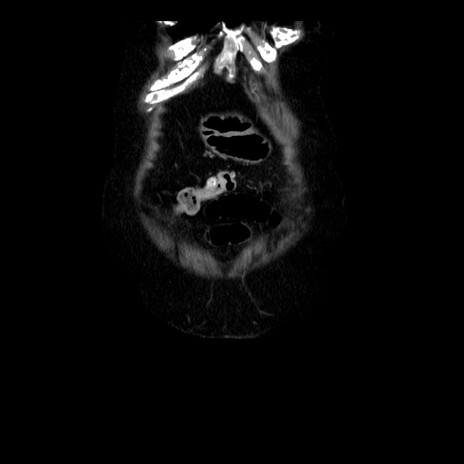

横断像